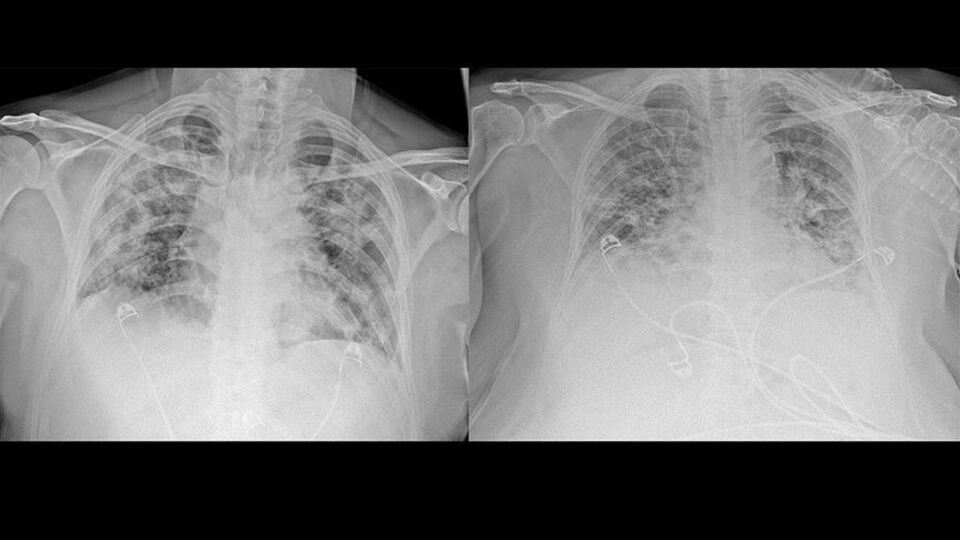

AA, Ankara Şehir Hastanesinde Kovid-19 tedavisi gören hastalara ait akciğer görüntülerine ulaştı. Görüntülerde, hastalığın ne kadar hızlı ilerlediği ve akciğerleri nasıl tuttuğu ortaya çıktı.

Prof. Dr. Karalezli, koronavirüs tedavisi gören hastalara ait akciğer görüntülerinden hastalığın yol açtığı tahribatı ve hastalar üzerindeki etkileri anlattı.

Normal akciğer görüntüleri ile koronavirüs hastalarının akciğer görüntüleri arasında ciddi farklar bulunduğunu belirten Karalezli, şu bilgileri verdi:

"İnsanların aradaki farkları anlamaları için her iki akciğer görüntülerine de yer verdim. Görüntülerdeki beyazlıklar akciğerdeki tutulumu gösteren görüntüler ne yazık ki. Bu hastalar yoğun bakım hastaları. Filmler birbirine az çok benzeyen şekilde. Altta yatan hastalığı olanlarda ise daha kötü seyrediyor."

Kliniğe yeni başvuran bir hastanın, 5 Ağustos'ta çekilen tomografi görüntülerindeki tipik koronavirüs görüntülerinin olduğunu ifade eden Karalezli, hastanın bir hafta içerisindeki tomografi görüntüsünde ciddi değişiklik olduğunu ve enfeksiyonun çok arttığını söyledi.